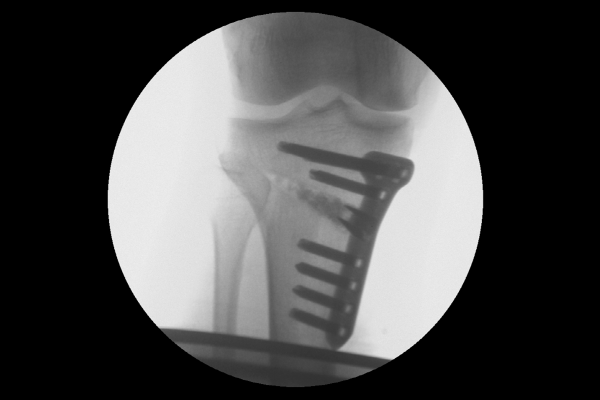

다리 전체 정렬을 확인하는 검사인 Scanogram 촬영 사진을 보시면, 오른쪽 다리 각도가 정상범위인 5도 이내를 벗어난 8.1도로 오다리 변형이 확인되었습니다.

수술은 성공적으로 마치게 되었고, 수술 후 X-RAY를 보면, 기존에 안쪽에 있던 체중선이 중간에서 살짝 바깥쪽으로 잘 이전되었고, 다리축이 일자로 교정되었음이 확인됩니다.